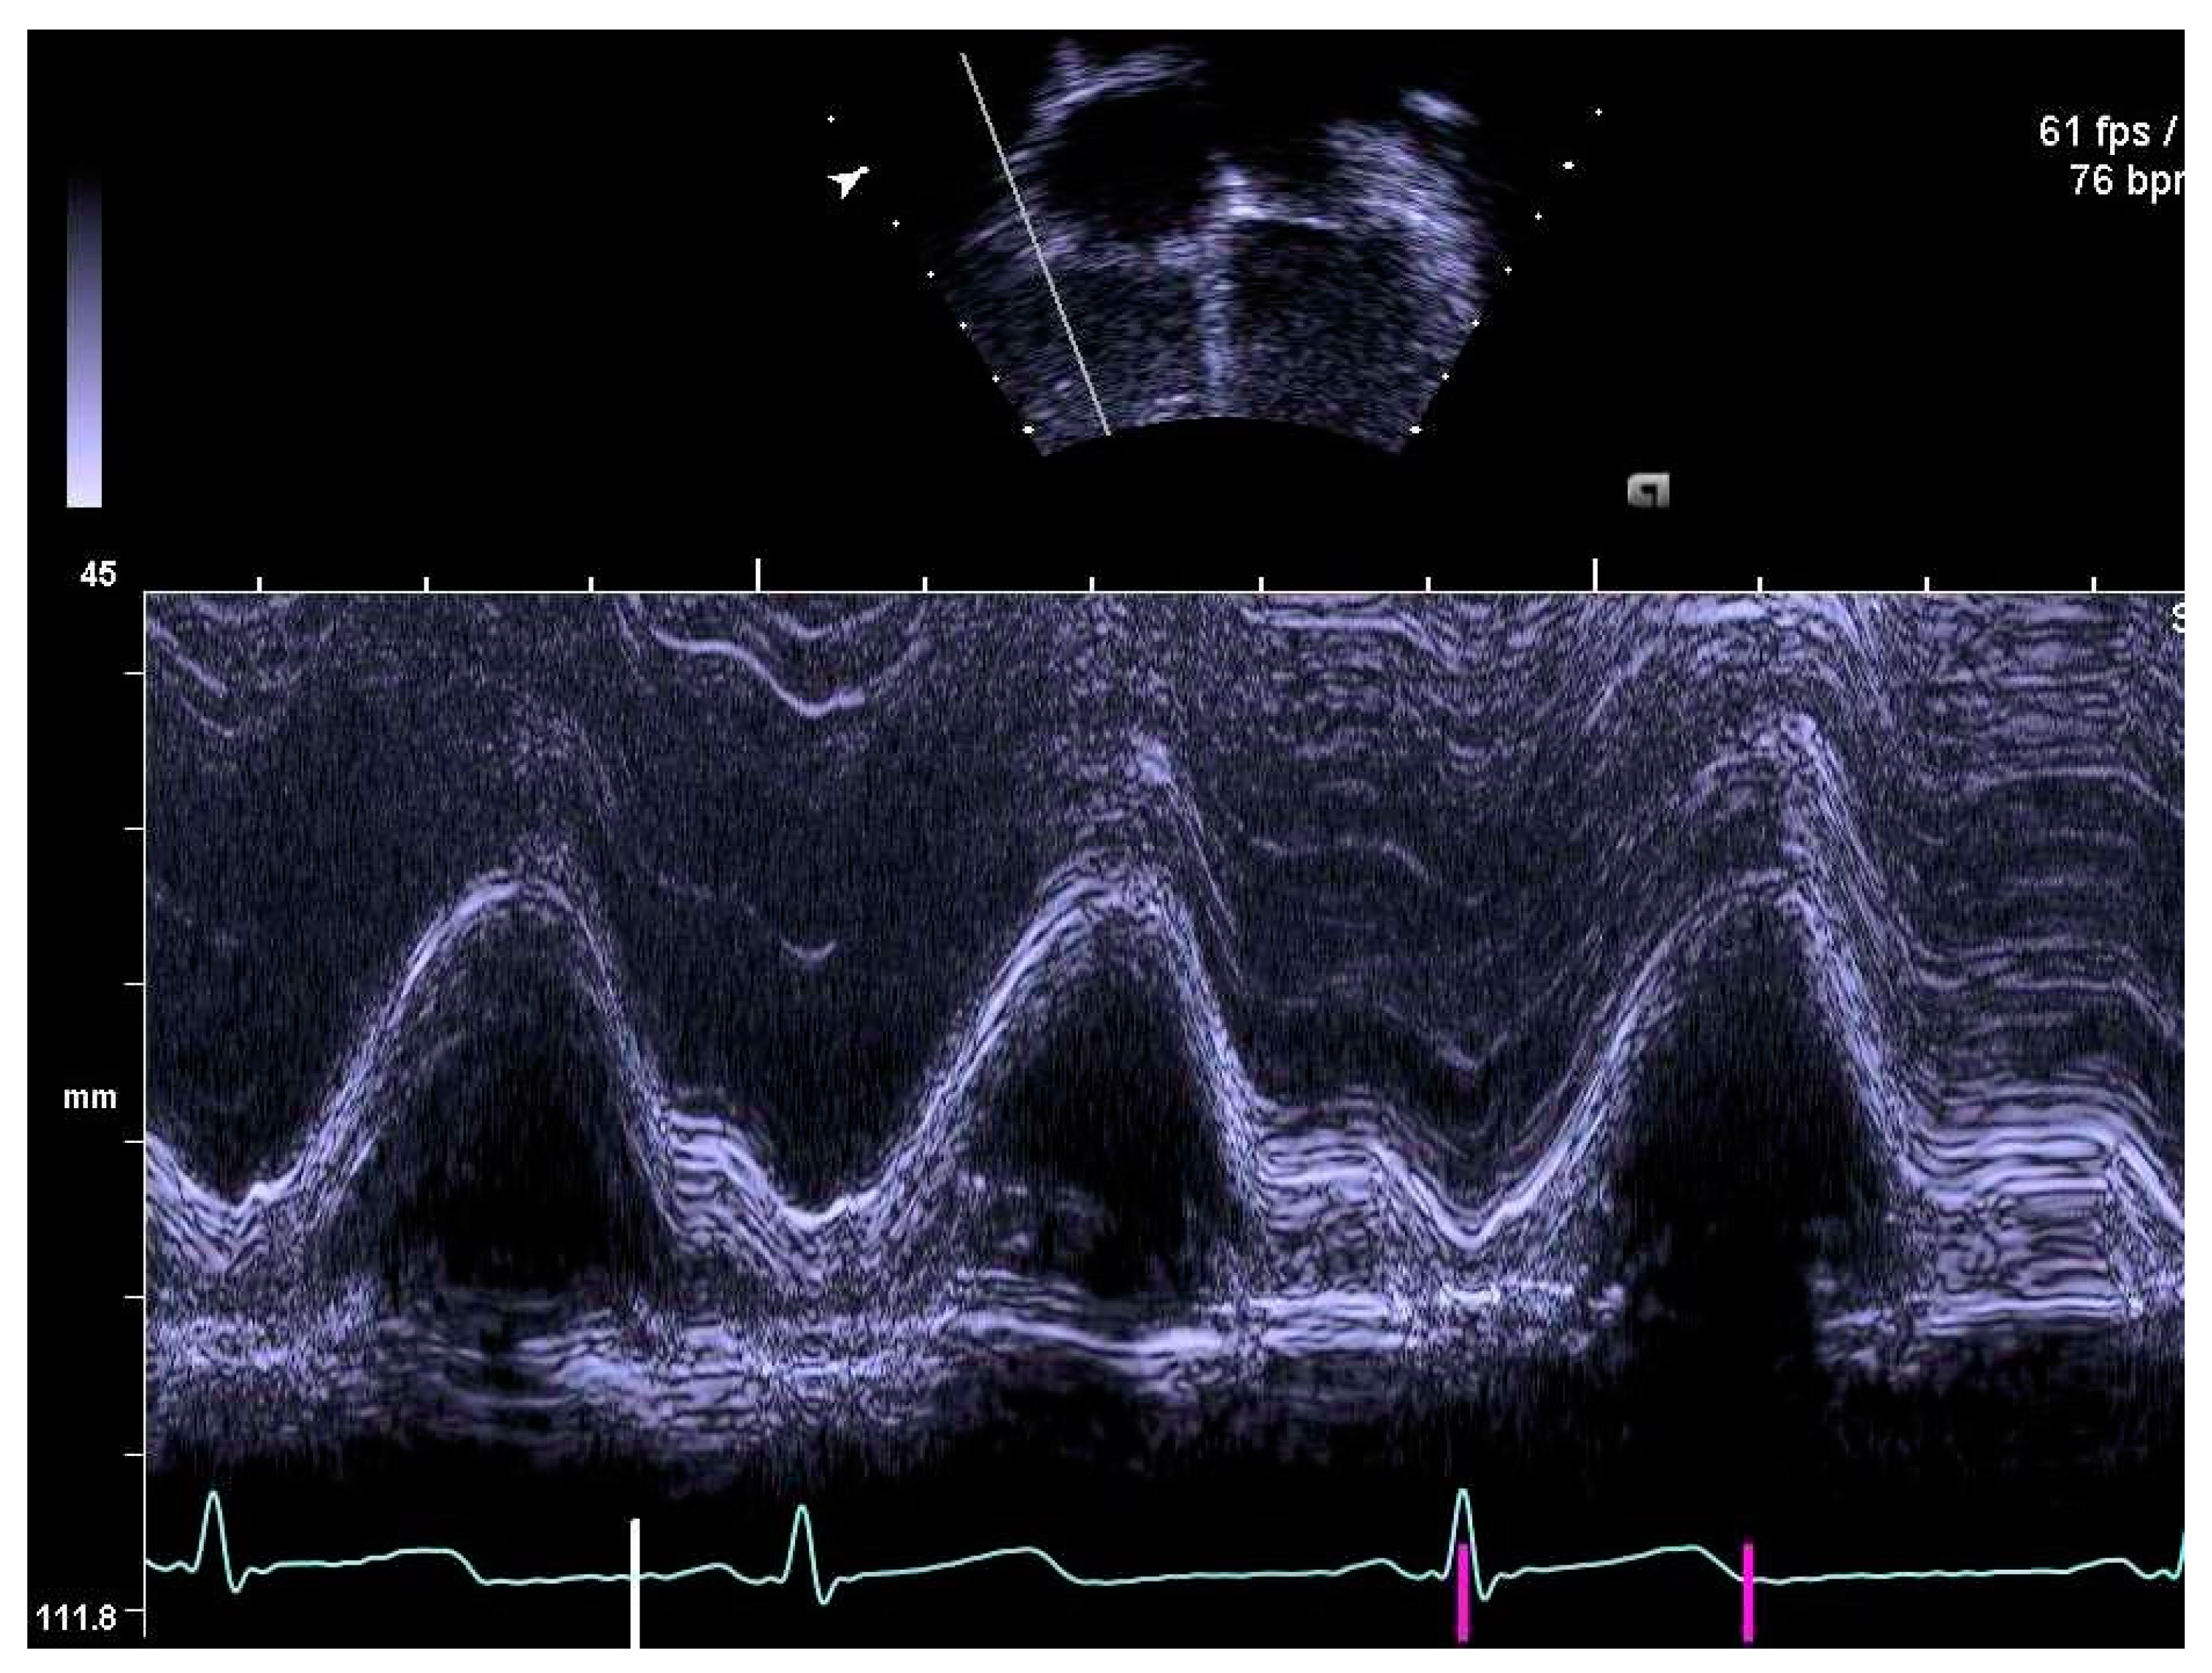

2.4. Determination of Right Heart Outcome Variables

3.4. Pulmonary Artery Diameters

3.5. Right Heart Systolic and Diastolic Functions